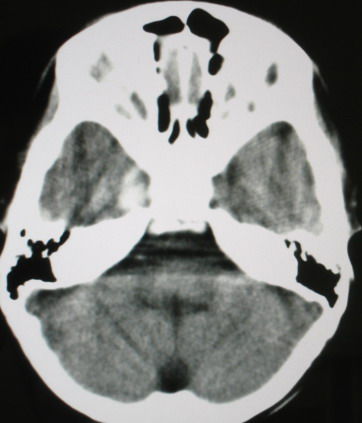

标题: PED0834:M8Y,考虑右侧海绵窦血管瘤 [打印本页]

标题: PED0834:M8Y,考虑右侧海绵窦血管瘤

m/8y,右侧眼睑下垂数天,头昏,无呕吐、无外伤史。无搏动性突眼。病人明天来增强。